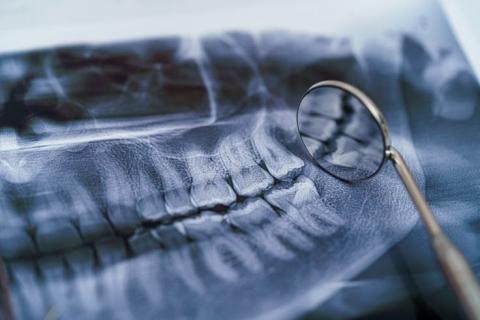

Основной инструмент стоматолога – зеркало, с помощью которого можно обследовать нужную область. Стоматологический зонд позволяет проверить состояние эмали зубов, найти кариозные поражения. Проводится перкуссия (лёгкое постукивание), чтобы определить подвижность зубов и наличие воспалений.

Рентгеновское исследование

Рентгенография давно стала одним из основных способов стоматологической визуализации. С её помощью врач видит снимки твёрдых тканей полости рта, на основании которых можно поставить точный диагноз и провести нужное лечение.

Если требуется восстановить объёмную структуру челюсти, то стоматологи пользуются методом 3D томографии или по другому КЛКТ челюстей. Помимо состояния зубов, по КТ определяют состояние: костной ткани, височно-нижнечелюстного сустава, гайморовых пазух.